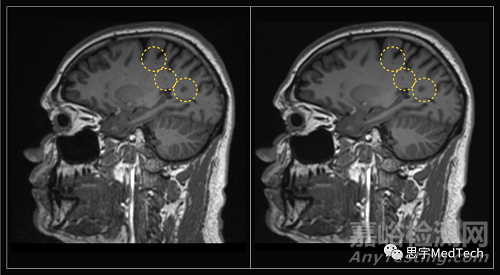

為了測(cè)試該技術(shù),該公司創(chuàng)建了一種快速M(fèi)RI協(xié)議(protocol),該協(xié)議會(huì)產(chǎn)生嘈雜的圖像,而新的AI系統(tǒng)能夠提高圖像的質(zhì)量。

▲(圖左為未使用AI技術(shù)形成的MRI圖像,圖右為Ezra Flash AI增強(qiáng)后圖像)